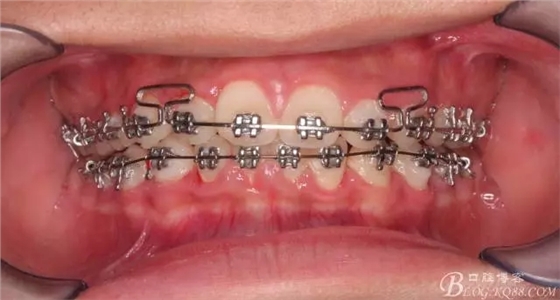

一晃快兩年了,我覺得關(guān)節(jié)重建及咬合穩(wěn)定,再加上患者的急迫愿望,我們拆除了矯正器。

640.webp (21).jpg

尖牙關(guān)系中性,磨牙關(guān)系中性,咬合鎖結(jié)良好!

15歲了,1米78的個(gè)頭,陽光帥氣的他,側(cè)貌堪比天安門國旗手的面型?。釘懒耍?p style="text-align: left;">640.webp (24).jpg